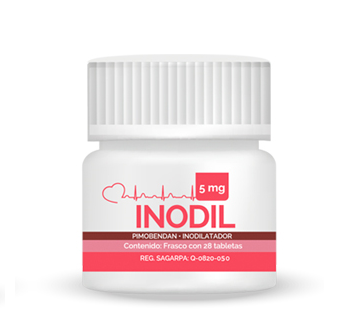

Estadio B2

Pimobendan 0.2-0.3 mg/kg PO c/12 hrs

Inhibidor de la ECA o espirinolactona

Estadios C y D

Furosemida

Pimobendán

Enalapril/Benazepril/Quinapril

Espirinolactona

Vasodilatadores